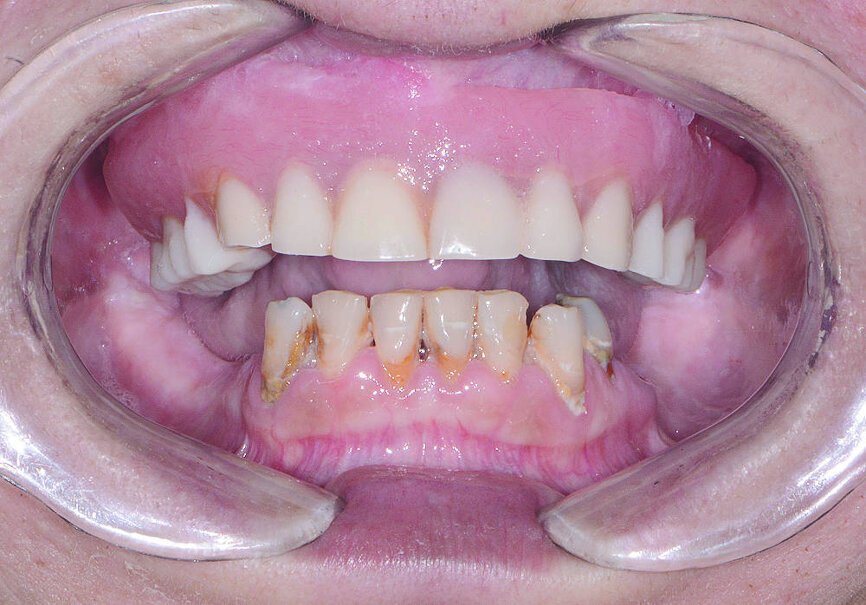

Une patiente dans la cinquantaine a consulté mon cabinet pour le traitement de son maxillaire édenté et de ses dents mandibulaires extrêmement déchaussées et cariées (Figs. 1 et 2). La patiente était une grande fumeuse, n’avait consulté aucun dentiste depuis plusieurs années, et négligeait de prendre soin de ses dents restantes en raison de l’inconfort et de la douleur qu’elle ressentait.

Fig 1 Vue préopératoire avec écarteur de lèvres

Fig 2 Vue préopératoire avec écarteur de lèvres, sans prothèse